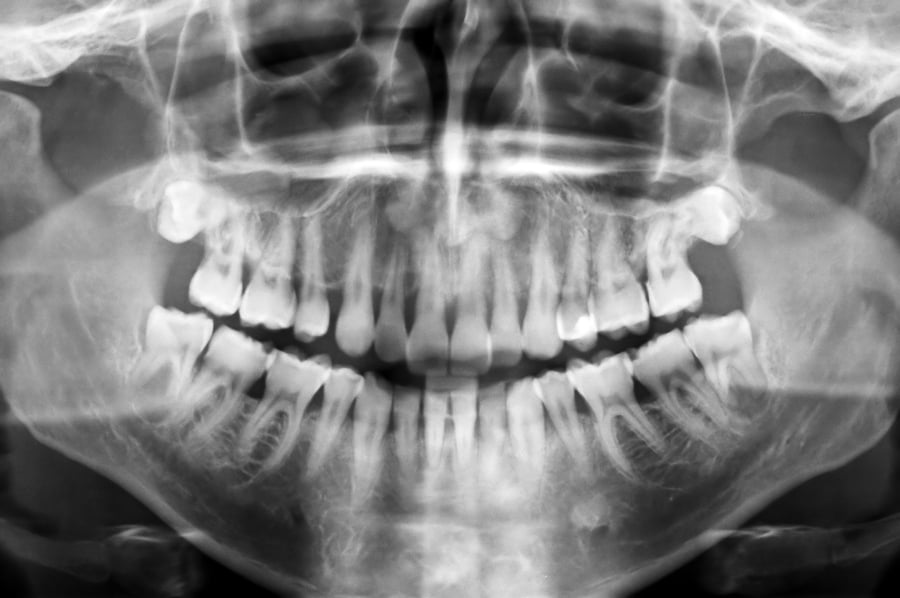

Corrective jaw surgery – or orthognathic surgery – is done to correct problems with oral function and/or appearance issues caused by jaws that are poorly aligned. Poor jaw alignment can be caused by jaws that are mismatched in size due to uneven jaw growth, or jaws that are shaped or …

Corrective jaw surgery, or orthognathic surgery, is a treatment process that includes both orthodontic and surgical treatment. It is used to treat adults who suffer with issues related to jaws that are poorly aligned, improperly positioned or mis-matched in size. These jaw discrepanci …

Corrective jaw surgery – also called orthognathic surgery – is done to correct jaws that are misaligned or have grown unevenly, causing problems with oral function and/or appearance. It is generally a collaborative process, involving a Singapore oral and maxillofacial surgeon, an orth …

Do you have a malocclusion – such as an overbite, underbite crossbite or openbite that cannot be resolved with braces or other orthodontic treatment? Perhaps you've been told by your orthodontist or dentist that your issue stems from misaligned or mismatched jaws? If so, you've probab …